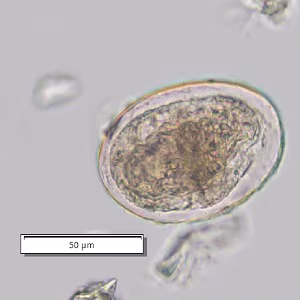

A 29-year-old man sought medical attention with his health care provider with a complaint of itchy maculopapular rash on several areas of his body. He reported travel to the Philippines, where he swam in fresh water while visiting the islands of Luzon and Mindanao. His health care provider requested a stool specimen for ova and parasite (O & P) testing. The sample was concentrated by the formalin-ethyl acetate method, and a wet mount smear made from the sediment and examined. A few objects of interest were detected. Figures A and B show the same object at different focal planes and Figures C and D show another object, also at different focal planes; both objects shown are at 200x magnification. What is your diagnosis?  Based on what criteria?

Figure A